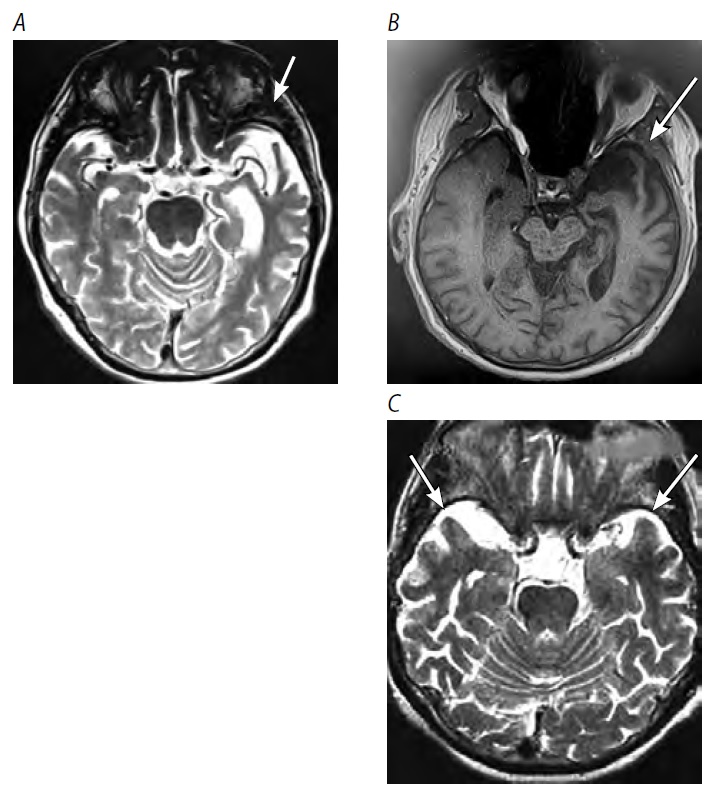

Как и при поведенческом варианте ЛВД, для сППА характерны такие симптомы, как неуместная эмпатия или её отсутствие, социальная расторможенность, «плоское» чувство юмора и патологическое пристрастие к сладкому. Понимание и осознание собственного дефекта часто кажется сохранённым, но может быть поверхностным или неполным. По мере прогрессирования заболевания могут появляться симптомы паркинсонизма. Нейровизуализационным признаком является чаще асимметричная (реже — симметричная) атрофия, затрагивающая, главным образом, передние отделы (полюс) височных долей мозга (рис. 3).

Рис. 3. МРТ головного мозга при сППА. Стрелки — атрофия (А, В — асимметричная, С — симметричная) передних отделов височной доли. / Fig. 3. Brain MRI of a patient with sPPA. Arrows indicate atrophy (А, В — asymmetrical, С — symmetrical) of the anterior temporal lobe.